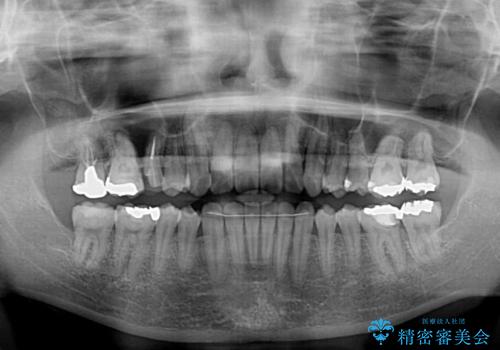

- 捻れた前歯が飛び出しており、口が閉じにくいとのことで来院された患者様です。

出っ歯というわけではないものの、前歯の捻転により口唇が押し出されている状態でした。

親知らずを抜去し、歯列全体を後方に移動させつつ、IPR(歯と歯の間を削る)でスペースを獲得し、インビザラインを用いて叢生を解消しながら前歯の突出を改善することとしました。

インビザラインは、患者様の協力無しには成立しない治療ですが、しっかりと装着時間を遵守してくださり、1年弱で治療を終えることができました。